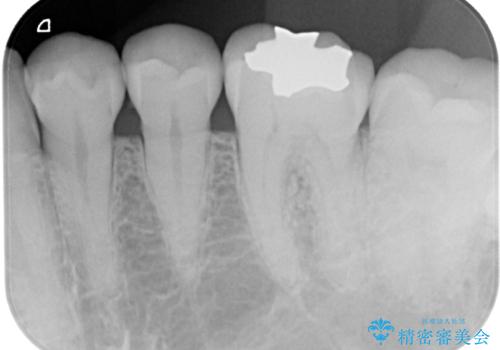

上顎左側第一大臼歯

下顎左側第一大臼歯

に入っていた保険診療の銀歯(メタルインレー)を、精度の良いゴールドインレーへやり替えを行いました。